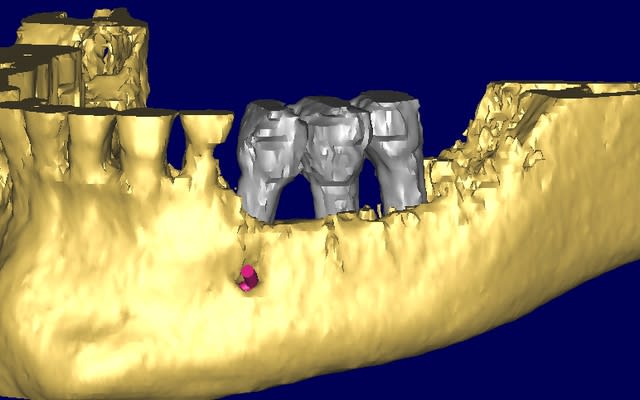

le cas n'est déjà pas facile...

il faut explanter tous le secteur 3 et 4

mais quid de la gestion osseuse ?

pour la gestion osseuse, je pensais utiliser des mesch titane et comblement avec os humain.